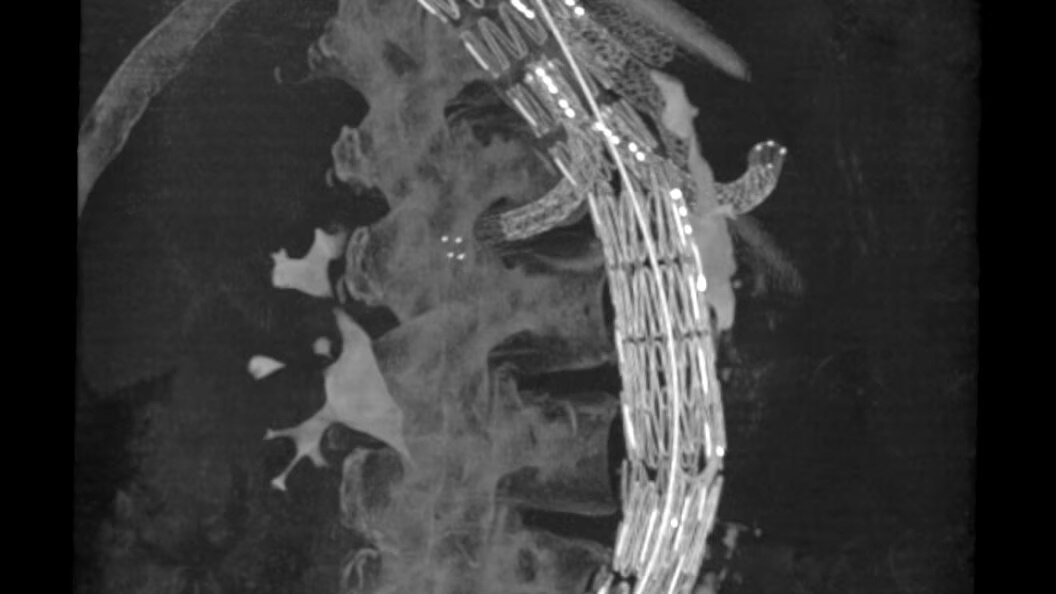

Enhance your clinical capabilities

Enable flexible cone-beam computed tomography (CBCT) even on obese patients and adapt to constantly evolving procedures and techniques.